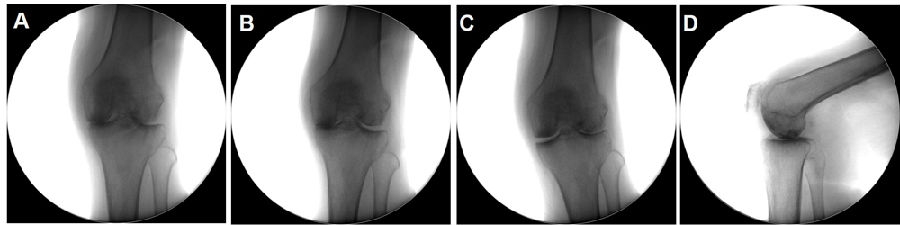

Case3:一期Bi-UKA治疗双间室OA

术前动力位片

术前透视。A.模拟负重位B.内翻应力位C.外翻应力位D.侧位

手术切口与暴露。A.膝前正中切口B.髌旁内侧入路C.内侧、外侧股骨髁磨损,ACL功能正常

内侧单髁置换。A.截骨完成B.安装内侧假体,等待骨水泥凝固C.假体安装完成

外侧单髁置换。A.按照外侧假体,等待骨水泥凝固B.内外侧单髁假体安装完毕C.切口及引流

术后透视。A.正位B.侧位

术后1X-ray

术后1周下肢功能